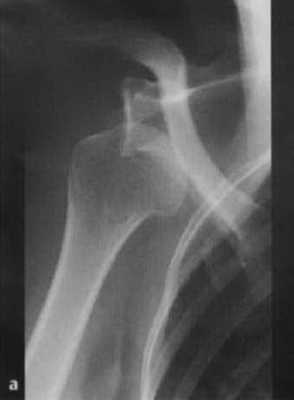

а, b Задний вывих плечевого сустава у женщины 45 лет после падения с велосипеда, (а) Рентгенологическое исследование правого плечевого сустава. Суставная щель в прямой проекции не визуализируется, плечо ротировано медиально.(b) Y-проекция четко демонстрирует задний вывих.

- Рентгенологическое исследование в двух проекциях: прямая тангенциальная (касательная) проекция суставной полости и чрезлопаточная проекция.

Передний вывих: головка плечевой кости расположена кпереди и книзу, обычно ниже клювовидного отростка; в редких случаях она может находиться на нижней границе суставной полости.

Задний вывих: головка плечевой кости перекрывает границу суставной полости; суставная щель не визуализируется.